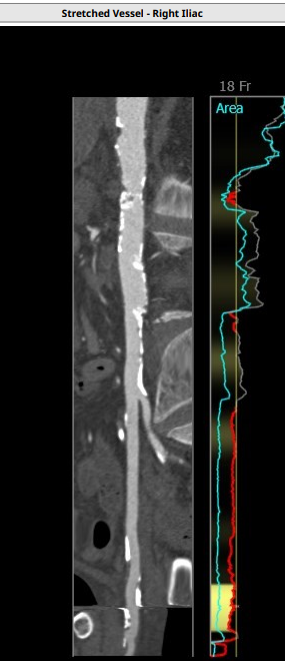

本例患者出现循环崩溃的原因较为罕见。术前分析时,术者认为患者心功能尚可,解剖上无特殊难点,唯一要注意的是患者因长期透析导致腹主动脉严重钙化狭窄,担心大鞘通过有困难。故特意选了23号瓣膜搭配18大鞘,术中小心操作,避免腹主动脉破裂的可能。

病人为三叶瓣,重度钙化,瓣环径为21,LVOT21.1,左冠高度11.3,右冠15.4,瓦氏窦均径在27左右,STJ26.3,升主无明显扩张,整体结构偏小,术前经综合评估,使用18F艾普特大鞘,venusA23号瓣膜预装。

入路